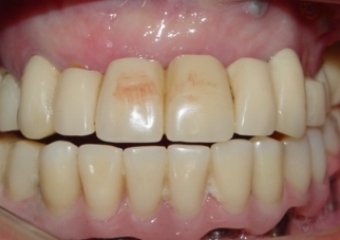

Imagem Próteses Provisórias Fixas Superior e Inferior , em 2011 - Clínica Cliniface

Imagem Próteses Provisórias Fixas Superior e Inferior , em 2011